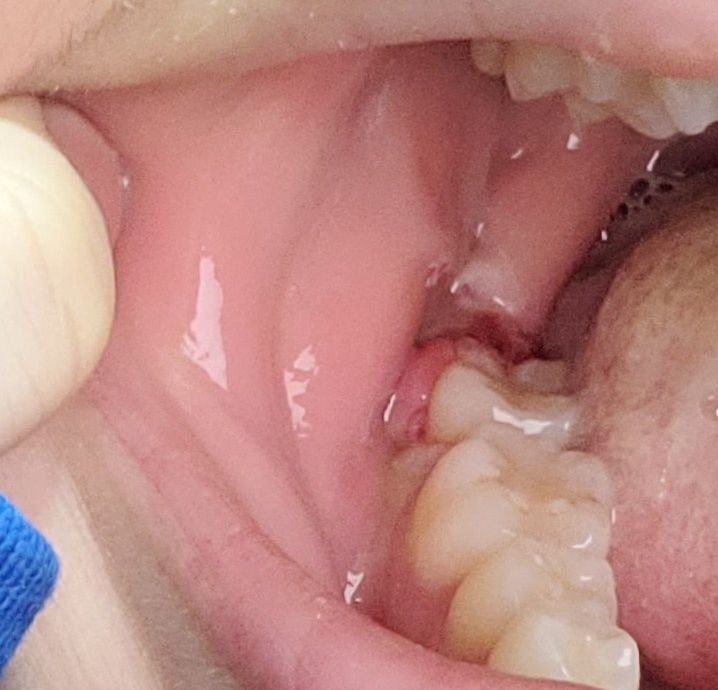

사랑니 실밥 제거 후 출혈이 있고 잇몸 상태가 넘 안좋은데 괜찮나요?

왼, 오 발치부위를 5일차인 오늘 실밥 제거를 했는데요. 실밥 뽑고나자마자 입안에 피가 잔뜩 났어요ㅠ 치과에선 그냥 거즈로 슥 닦고 주사기로 이물질 제거하는 법 알려주더라구요..!

아무튼 1번째 사진(왼쪽)은 어금니 잇몸까지 띵띵 부어있어서 양치도 못하고 아직 죽밖에 못 먹어요. 2번째 사진(오른쪽)은 피가 젤 많이 났었는데 지금은 조금씩만 나는 상태에서 찍었어요.

대부분 실밥 풀면 구멍만 뿅 뚫려있던데 저는 시뻘겋게 잇몸 부어있고 피도 나서 걱정이네요,,

왼쪽인데 여기가 피는 덜나도 붓기가 훨씬 심해요

오른쪽은 붓기는 따로 없는데 실밥 제거 시 피 많이 남

원래 실밥 풀면 실 들어가 있던 자리로 피가 스며 나오는 경우가 종종 발생합니다. 그냥두면 저절로 멈춥니다. 발치한 자리는 정상적으로 아물고 있는 범주에 속합니다.

해당 부위는 잘 아물고 있는 것으로 보입니다. 발치한 부위에 이물질이 있거나 한다고 해도 억지로 제거하려고 하지 않는 것이 좋습니다. 제거를 하려다 상처가 생기게 되면 치유가 늦어질 수 있기 때문입니다.

발치 5일차면 혈병은 이미 잇몸 치유를 위한 세포로 바뀐 상태입니다

출혈이 다소 있고 치유가 조금 느리긴한데 걱정할 정도는 아닌 듯 합니다